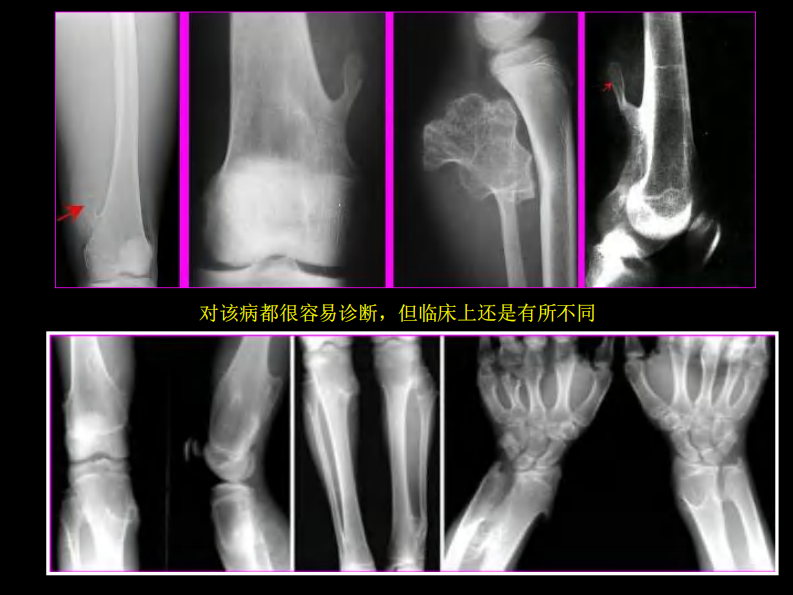

骨肿瘤影像学诊断.pdf